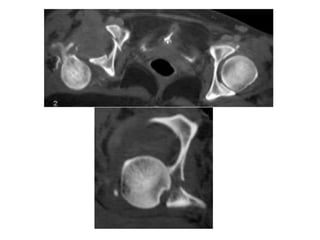

La tomodensitométrie: permet de faire un bilan précis

des lésions ostéo-chondrales infra-radiologiques et de

planifier un éventuel geste chirurgical, mais elle ne doit

pas retarder la prise en charge.

Il est à noter que les lésions chondrales et

ostéochondrales sont largement méconnues par les

radiographies standards alors qu’elles jouent

probablement un rôle important dans le développement

d’une arthrose ultérieure, d’où l’intérêt de réaliser cet

examen de manière différée mais systématiquement,

même si la réduction semble parfaite.